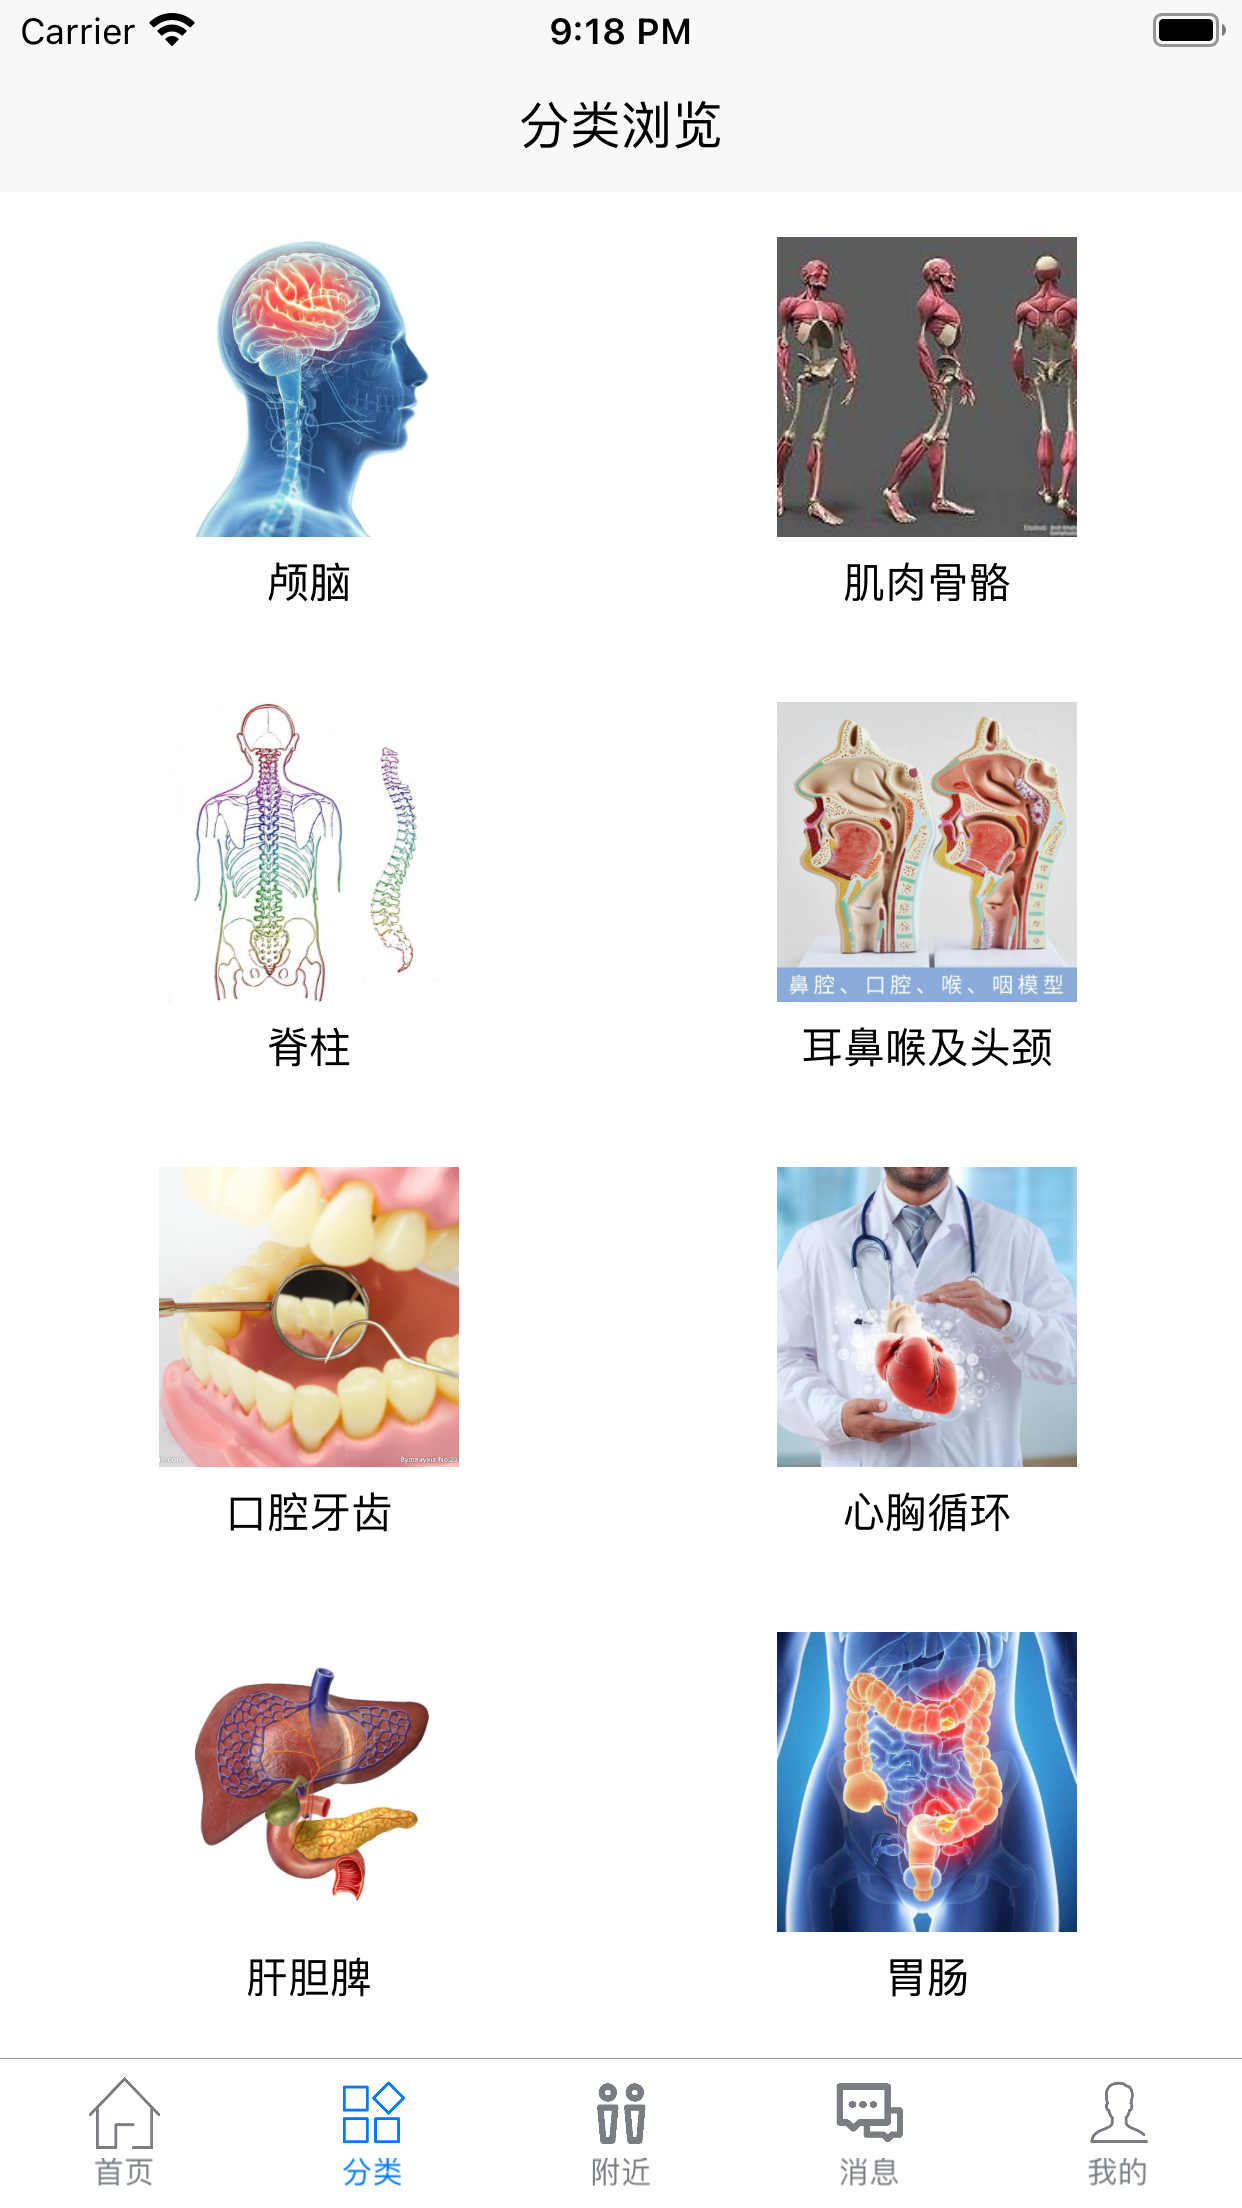

按类别组织

按人体大体部位进行分类,有效的对各种病例进行组织,方便预览,回顾。